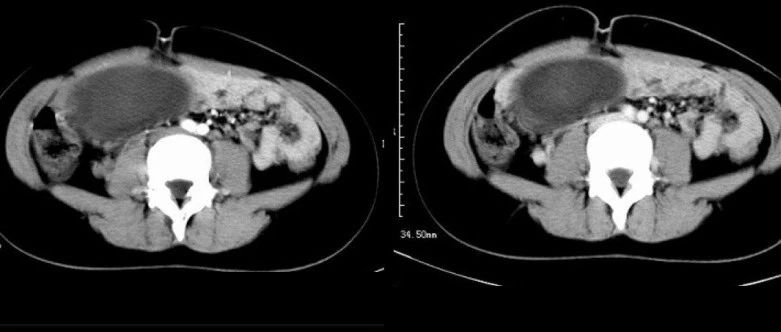

仅供医学专业人士阅读参考确实有点“恐怖”去年,恐怖大师温子仁带来了一部《致命感应》。电影中,女主角身边莫名发生死亡事件,她的丈夫、朋友都被极其残忍的杀害。女主角隐约觉得这和自己童年想象出来的恶魔有关。后来多方调查发现,女主角“想象的恶魔”是真实存在的,它是女主角头上一个丑陋、诡异的畸胎瘤!图1 图片来源:电影《致命感应》原来女主角小时候就有这个畸胎瘤,但是因为长在头上,为了不伤害大脑,医生只能切除大部分畸胎瘤,剩下的畸胎瘤一直潜伏在女主角身上,等到她因为受到情感伤害后又“觉醒”,之后操纵女主角做下了种种恶行。...